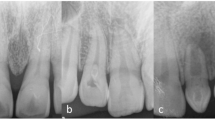

The distribution of the DI cases according to sex, tooth type, bilateral occurrence, and Oehlers classification is presented in Table 2. Bilateral DI was detected in 24.3% of the affected patients. Most of the DI were Oehlers type I (80%), followed by type II (17.8%) and type III (2.2%). In one invaginated tooth, the crown was not completely developed, and the extent of invagination could not be determined. Thus, the DI type was considered as “not-applicable”, and the tooth was excluded from the DI type analysis. DI type was not associated with sex, nor tooth type (P > 0.05). Figure 1 shows representative images of each DI type.

In 30% of the invaginated teeth, a discontinuity was observed in the radiopaque outline of the DI. This was apparent in a single or multiple CBCT sections. The DI was teardrop in shape in 33 teeth (72%) and fissure-like in six teeth (13%), while only minor invagination beyond the cingulum pit was observed in seven teeth (15%). In parallel with the DI morphology and extension, the root canals were observed to bifurcate and branch around the DI in 36 teeth (78.3%) (Fig. 1A,D), appeared C-shaped in two teeth (4.3%) (Fig. 1I), and were normal in eight teeth (17.4%). CBCT sagittal sections were found to be the most useful for DI detection and evaluation.